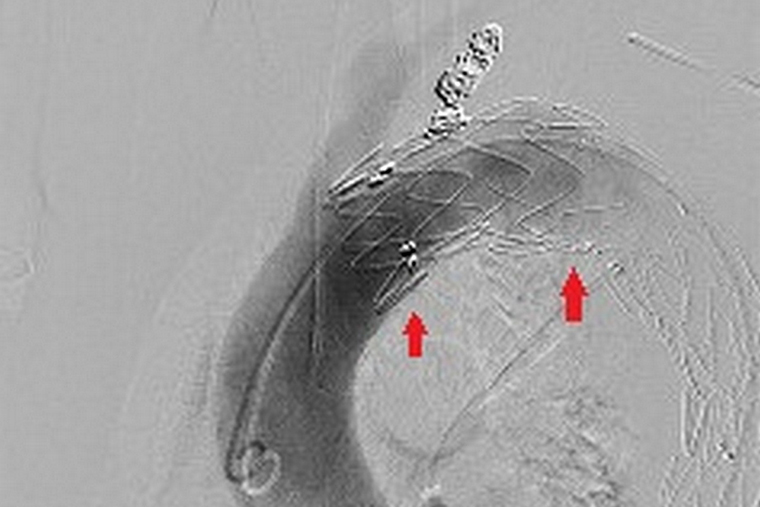

▲利用穿刺導引支架至動脈瘤位置,將主動脈支架展開,達到避免動脈瘤破裂之風險。(圖/台北慈濟醫院提供)

宋鎮宇解釋,以現今治療方式來說,大多數的胸主動脈瘤及腹主動脈瘤,解剖構造評估適合便可考慮主動脈支架手術。醫師將從鼠蹊部劃一個3至5公分小切口,利用穿刺股動脈導引支架至動脈瘤位置,再將包覆支架的人工血管展開,讓血液順利通過,達到避免動脈瘤持續擴大破裂之風險,成功率達9成,且對於年紀較大或是本身有心肺疾病的患者,可以大幅減少手術風險及術後併發症。